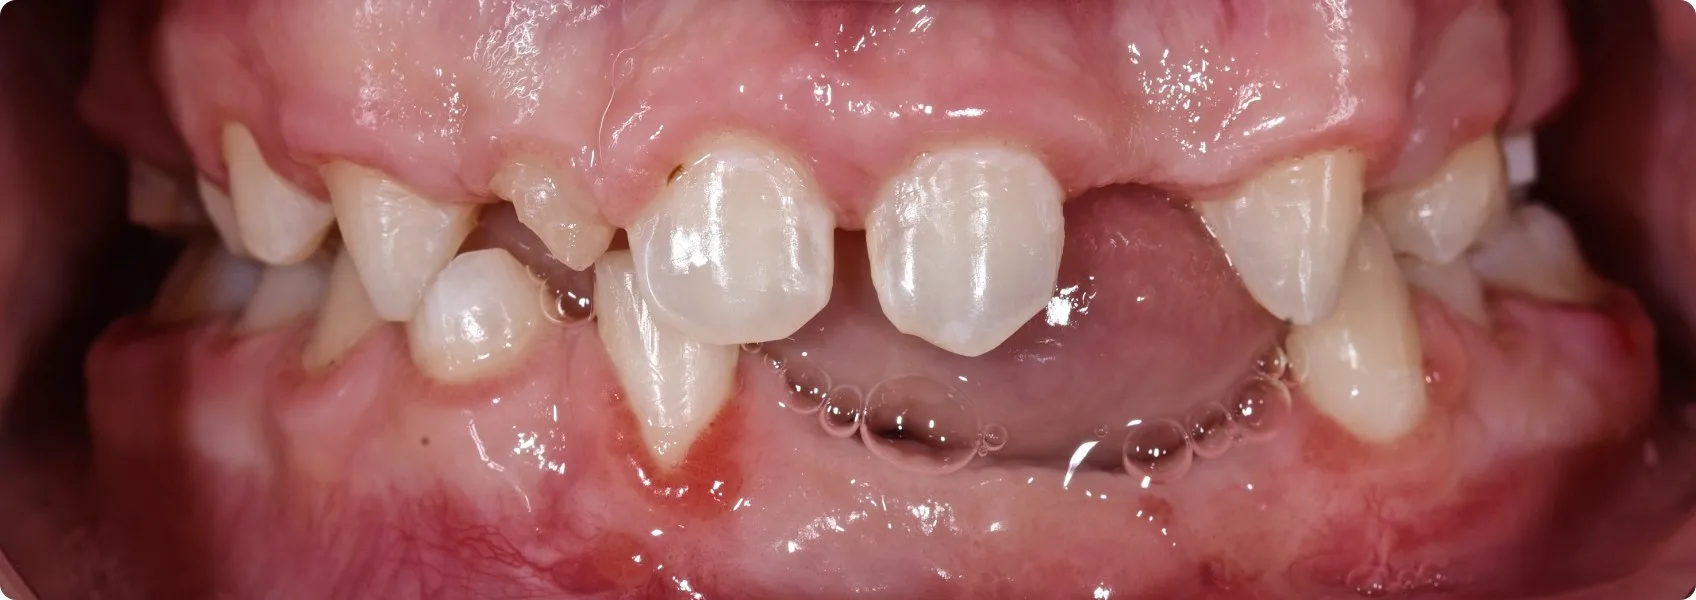

To historia młodego Pacjenta, dla którego uśmiech stał się przyczyną ogromnych kompleksów. Powodem była dysplazja ektodermalna – rzadka choroba genetyczna.

Dysplazja ektodermalna charakteryzuje się nieprawidłowym rozwojem tzw. tkanek pochodzenia ektodermalnego. Do tych tkanek należą między innymi skóra, włosy, paznokcie, gruczoły potowe, ale także i zęby.

W wyniku dysplazji ektodermalnej zęby Pacjenta nie wykształciły się prawidłowo: były niewielkie, niektóre o stożkowatym kształcie, występowały między nimi liczne przerwy.